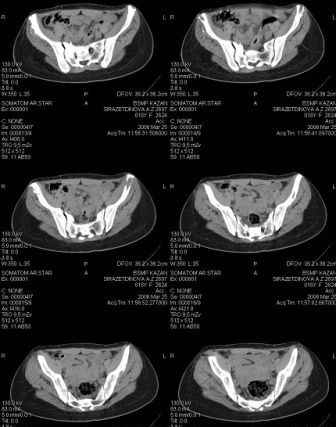

Re: Неправильно сросшийся перелом костей таза

Anton Kovalenko 10 Апрель 2006, 11:49

Предоставляю срезы. Если пациентку функционально ничего не беспокоит, стоит ли навязывать ей лечение.

Рунков А.В. 13 Апрель 2006, 12:15

Уважаемый Антон,

Если пациентка не собирается жить половой жизнью и вообще собирается в моностырь, то пожалуй, я бы согласился с Вами и навязывать лечение не стал.

Но если девочка более активна в жизни, я бы рекомендовал ликвидировать укорочение и вернуть тазу естественную форму.